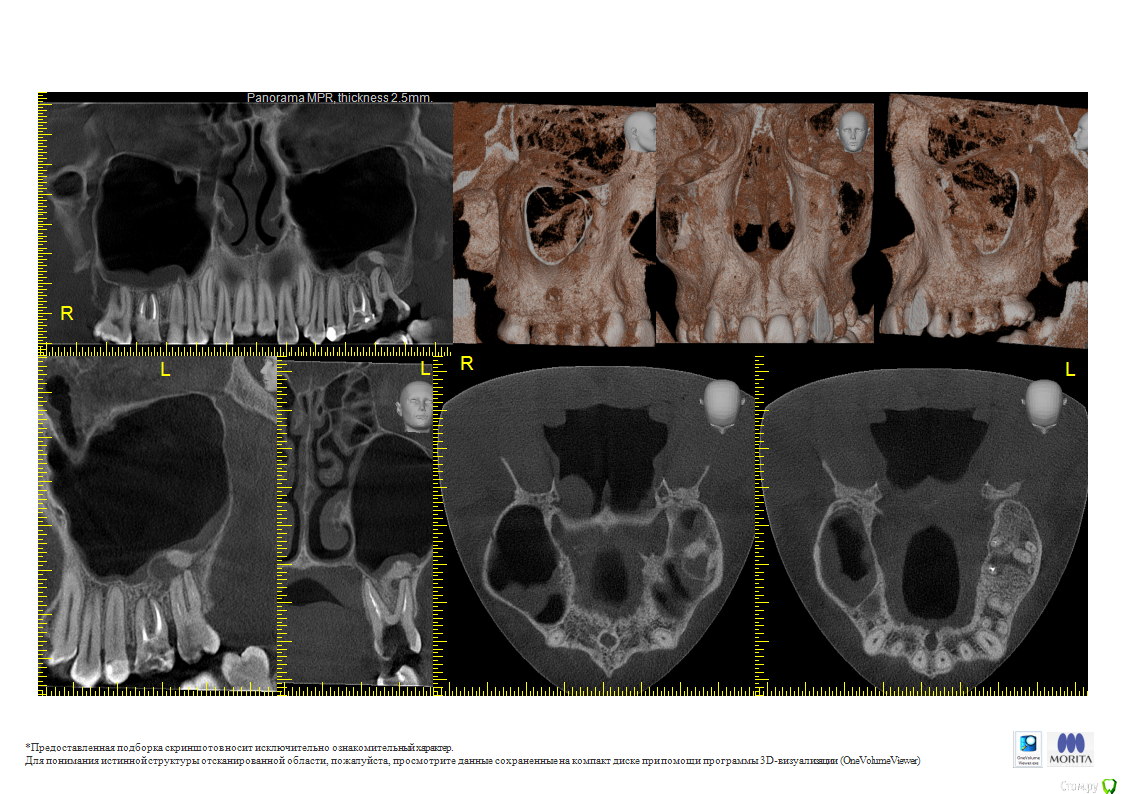

Misha86 Опубликовано 3 марта, 2016 Поделиться Опубликовано 3 марта, 2016 (изменено) Здравствуйте, прошу Вашей помощи и консультации. Поставили диагноз, киста зуба проросшая в гайморову пазуху, врач сообщил, что необходимо делать операцию по удалению кисты и чистке самой пазухи, при этом под удаление 27 и 26 зуб. КТ прикрепляю. И можно ли удалить только 27 зуб от которого и пошла киста или же 26 тоже под удаление? А так же волнует вопрос гайморотомии, стоит ли ее вообще делать, можно ли просто обойтись просто удалением? Изменено 3 марта, 2016 пользователем Misha86 Ссылка на комментарий

Misha86 Опубликовано 3 марта, 2016 Автор Поделиться Опубликовано 3 марта, 2016 Подождите, нужно начать с грамотного эндодонтического лечения. С большой вероятностью все пройдет. Ну уж если не поможет, тогда потом хирургия.Подскажите, а если киста проросла в пазуху? 2.7 удалять точно? Может ли киста выйти с семеркой и не придется чистить пазуху и делать гайморотомию? Ссылка на комментарий

Гарриевич Опубликовано 4 марта, 2016 Поделиться Опубликовано 4 марта, 2016 Удаления не нужны. Достаточно качественно пролечить 27 зуб и перелечить 26 зуб и с большой вероятностью "киста" исчезнет Ссылка на комментарий

DmitrySH Опубликовано 4 марта, 2016 Поделиться Опубликовано 4 марта, 2016 Да, 16 зуб ( справа) тоже требует ревизии каналов Ссылка на комментарий